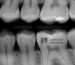

In children’s imaging of the face and jaw, due to the high sensitivity of areas near the brain and eyes, there is a strong need for safer, lower-radiation methods. Using digital imaging and 3D imaging technologies can help reduce radiation dose. Additionally, paying attention to specific techniques for imaging the face and jaw, such as using high-precision images and short exposure times for capturing images, can help prevent radiation dose damage. Finally, opting for alternative methods like ultrasound can also help reduce radiation dose.

Children’s imaging of the face and jaw has seen advancements in recent years, leading to a significant reduction in radiation dose. These advancements include digital devices that can automatically adjust radiation dose. These devices can automatically adjust the radiation dose based on the imaging requirements and minimize it. Furthermore, using specific techniques for imaging different areas of the face and jaw, such as CT imaging, reduces the need for high radiation doses. These new approaches can significantly improve safe imaging for children and reduce radiation dose risks.

To reduce radiation dose in children’s imaging of the face and jaw, advanced technologies like digital imaging can be used, which require lower radiation doses. Additionally, using 3D imaging systems, specific device settings to minimize the child’s exposure time to radiation dose, and filtering the radiation dose to the minimum also contribute to radiation dose reduction.